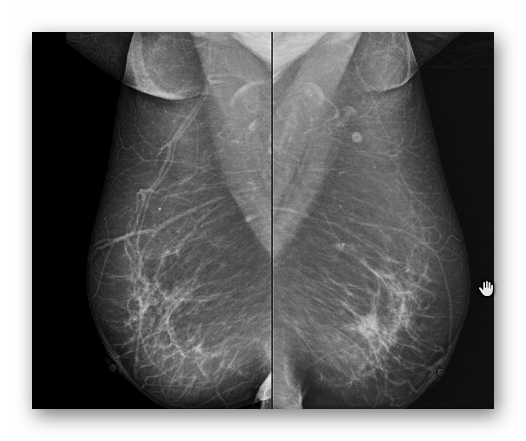

SUTEK PRAWIDŁOWY

MAMMOGRAFIA